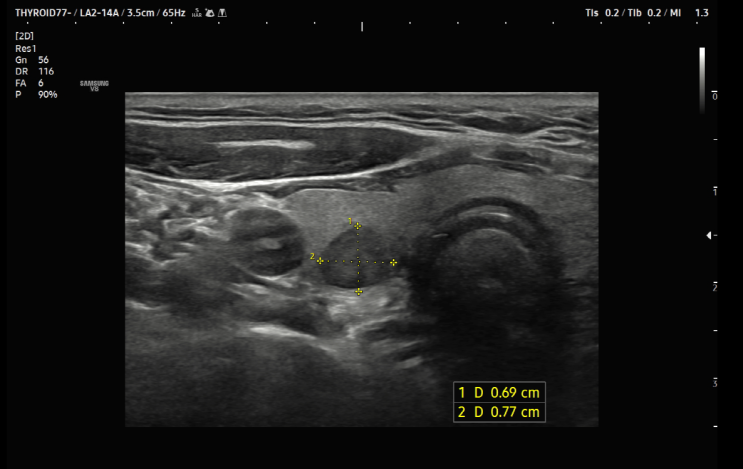

필수 건강검진 갑상선초음파, 서울으뜸내과 갑상선암 증례

#갑상선FNA #갑상선초음파 #서울으뜸내과 #왕십리내과 #상왕십리내과 #검진내과 #5대암검진 #검진초음파...